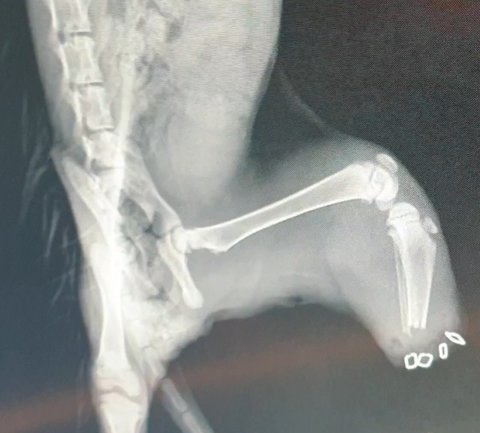

너무 어린 녀석입니다.

어쩌다 그물에 걸려서...

무릎 바로 아래를 잘라냈다고 합니다.